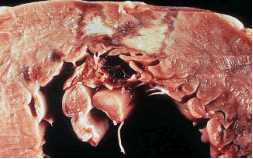

肺出血目前已公認腎臟發病原理為抗基底膜抗體型腎炎的免疫反應過程由於某些發病因素原發性損傷肺泡間隔和肺毛細血管基膜後者刺激機體產生抗肺基膜抗體在補體等作用下引起肺泡一系列免疫反應由於肺泡壁基膜和腎小球基底膜間存在交叉抗原故內源性抗肺基膜抗體又能與腎小球基底膜起免疫反應損傷腎小球肺表面瀰漫性出血切面可見水腫和陳舊的出血鏡檢見肺泡內出血肺泡腔內常有吞噬含鐵血黃素的吞噬細胞局灶性肺泡纖維組織增殖免疫螢光檢查顯示肺泡間隔和肺毛細血管基膜有免疫球蛋白和C3呈線狀沉積腎臟病理改變似急進性腎小球腎炎此外早期腎小球毛細血管呈局灶和節段性壞死後期腎小球周圍有淋巴細胞浸潤為一特點